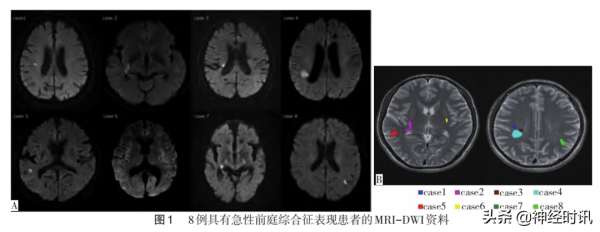

Eguchi團隊於2019年發表了更為詳細的前瞻性研究結果。他們研究2010年4月至2017年3月收入細野川總醫院的930例急性腦梗死連續病例,除外雙側半球、小腦及腦幹急性期梗死患者,最後668例入組。在668例單側半球急性梗死患者中,8例有前庭綜合徵表現,7例有眩暈,1例有頭動誘發的非眩暈性頭暈伴行走不穩。所有病例的急性前庭症狀均在2d內消失。8例患者的彌散成像(DWI)表現見圖1A,其中6例右利手患者病灶出現在右側半球,2例左利手患者病灶出現在左側半球,病灶疊加後集中區域見圖1B。他們認為,侷限於大腦半球前庭皮層網路的急性梗死能引起前庭症狀,病灶所在側別與手的優勢側基本一致。